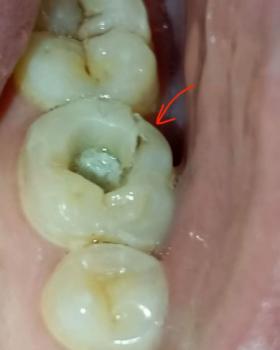

This image shows a patient wearing orthodontic braces with a large, painful ulcer on the inner lower lip. The sore has a yellowish center with surrounding redness and swelling, consistent with traumatic oral ulceration caused by repeated friction from brackets or archwire.

Single, well-defined ulcer on inner lower lip

Yellow or pale necrotic center

Red, inflamed surrounding tissue

Swelling of the lower lip

Brackets and wire in direct contact with affected area

Findings are suggestive of a traumatic mouth ulcer

Likely caused by continuous rubbing of braces during speaking and chewing

Orthodontic appliance–induced oral ulcer

Traumatic mucosal injury with secondary inflammation